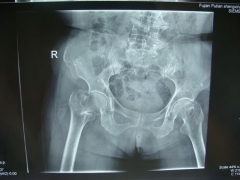

7月9日,莆田盛興醫(yī)院為一名89歲的女性髖部骨折患者順利實(shí)施了手術(shù)。   數(shù)日前,東……

近日,平海鎮(zhèn)90歲高齡的周阿婆即將出院。她感慨地對(duì)筆者說(shuō):“真沒想到我還能下床走路……